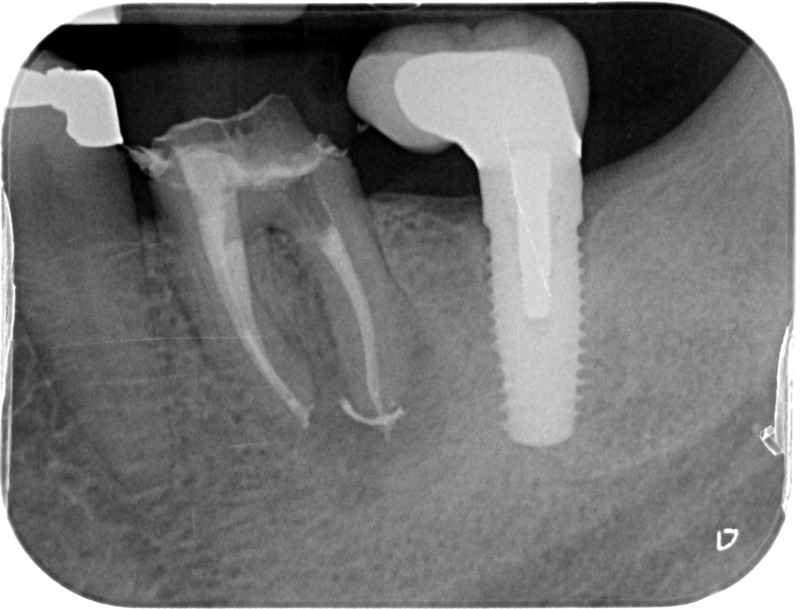

Après

• Traitement endodontique : Sous anesthésie locale et à travers la protection d’un champ opératoire nous accédons à la pulpe de la dent à soigner, puis aux canaux de ses racines que nous devons désinfecter. Ce soin nécessite l’élimination complète de la source de contamination (souvent la carie) parfois sous une ancienne reconstitution ou une couronne qu’il faut alors retirer. Une fois le nettoyage et la mise en forme des canaux réalisés, nous les obturons de façon hermétique avec un ciment et un matériau thermoplastique appelé Gutta Percha. Ceci afin d’empêcher une nouvelle prolifération bactérienne et d’assurer le maintien de la dent dans ses structures de soutien (ligament parodontal et os alvéolaire). L’ouverture effectuée au centre de la dent sera d’abord refermée avec un pansement provisoire avant d’envisager ensemble la reconstitution d’usage : un composite, un inlay-onlay ou une couronne.